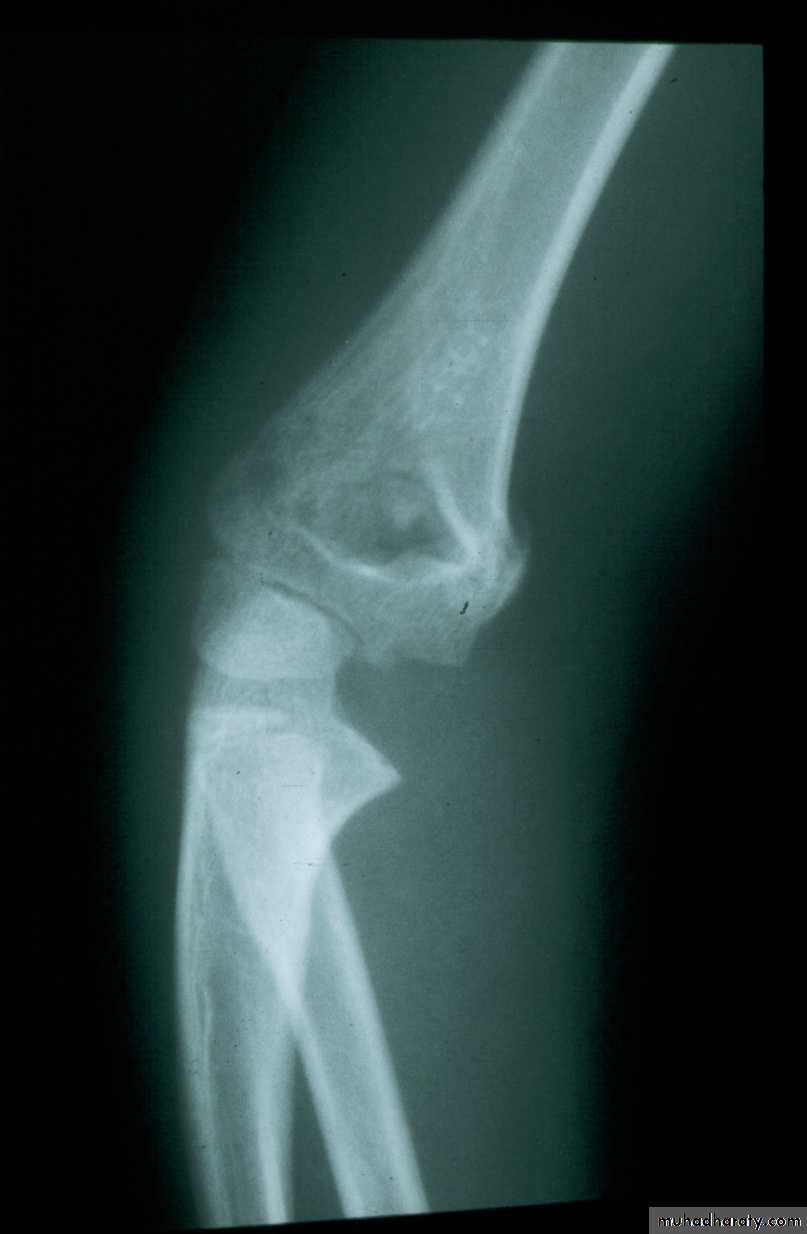

8 y.o.

Is this a simple extension

type supracondylar fracture ??

It also has

anterolatateraldisplacement !!

The distal fragment is

not flexed,but also it is not extended to any degree.

This also is a Type III Flexion Pattern.

What is differentabout this fracture?

But, if not recognized as such, it may be a problem.

This fracture was irreducible,

and required an open reduction !!!

There are some clues to these occult flexion injuries.

1. The distal fragment is not extended,

however,it may not be flexed to any degree.

It may be

rotated!!2. The distal fragment is in valgus.

3. The medial spike of the proximal fragment is usually posterior.

4. There may be clinical signs of ulnar nerve dysfunction.

Why are these fractures irreducible ?

The location of the proximal medial spike is critical.The medial spike

is pressing againstthe ulnar nerve.

It is also posterior to the

intermuscular septum.

What is the operative approach ?

It involves an anteromedial incision.